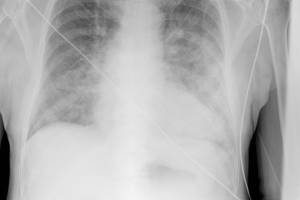

Добрый день. Проходила планово от института ФЛГ, мне через два дня сказали, что у меня подозрение на бронхит. Расстроилась очень и нахожусь в замешательстве, так как жалоб нет и симптомов тоже. Ни кашля, ни свистов/хрипов, грудная клетка не болит. К тому же я донор, постоянно сдаю кровь, никаких отклонений анализы не показывают. Но дело еще вот в чем: когда делали ФЛГ, попросили глубоко вдохнуть, а я не расслышала и наоборот выдохнула. Может из-за этого такие результаты, подскажите пожалуйста, переживаю очень. Спасибо.

Здравствуйте, Ольга! Переживать не надо – возможно ФГ выявила проявления хронического бронхита или признаки недавно перенесенной вирусной инфекции. Для уточнения ситуации – сходите к терапевту – пусть врач Вас послушает (имеется ввиду аускультация легких). Если есть изменения – врач назначит лечение. Берегите здоровье!

Здравствуйте, Ольга, в первую очередь необходимо сделать рентгенографию органов грудной клетки, спирографию с пробой с сальбутамолом.